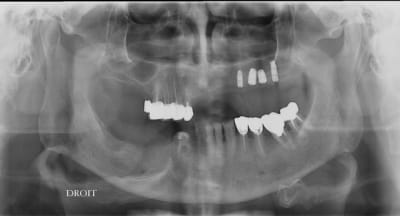

15/07/2009 à 23h52

pxav écrivait:

--------------

> le pano bof...

>

> --

> xbk

C'est quoi ton plan de traitement ????

--

;O)

16/07/2009 à 01h14

Chicot écrivait:

----------------

>

> C'est quoi ton plan de traitement ????

> --

> ;O)

rehabilitation max sup et inf

transvissée au max (amovo inamovible) refection 4 ccm restantes

prothese fixée à la mdble ccm sur 43

bruxisme prononcé

85 ans en pleine forme mais je fais en plusieurs fois pour ne pas trop le fatiguer.

--

xbk

16/07/2009 à 10h55

Merci pour cette expérience partagée. Belles photos. Merci aussi d'avoir l'honnêteté de présenter un cas qui ,s'il paraît franchement parfait sur les photos de chir, l'est un poil moins sur la pano (mais c'est qu'une pano). De toute façon avec une expérience comme la tienne la gestion prothétique se fera sans doute sans trop de soucis.

pour la prothèse, je ne me fais pas de souci mais la pose sur le pano me plait tres moyennement, alors qu'en bouche ça paraissait axé comme il faut.

mon souci c'est le stellitte du patient que j'ai retouché mais j'ai peur qu'il s'en serve violement